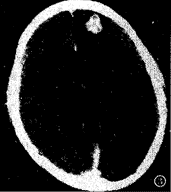

图2 为图1病人治疗后,病灶呈小结节状强化,周围水肿消失。